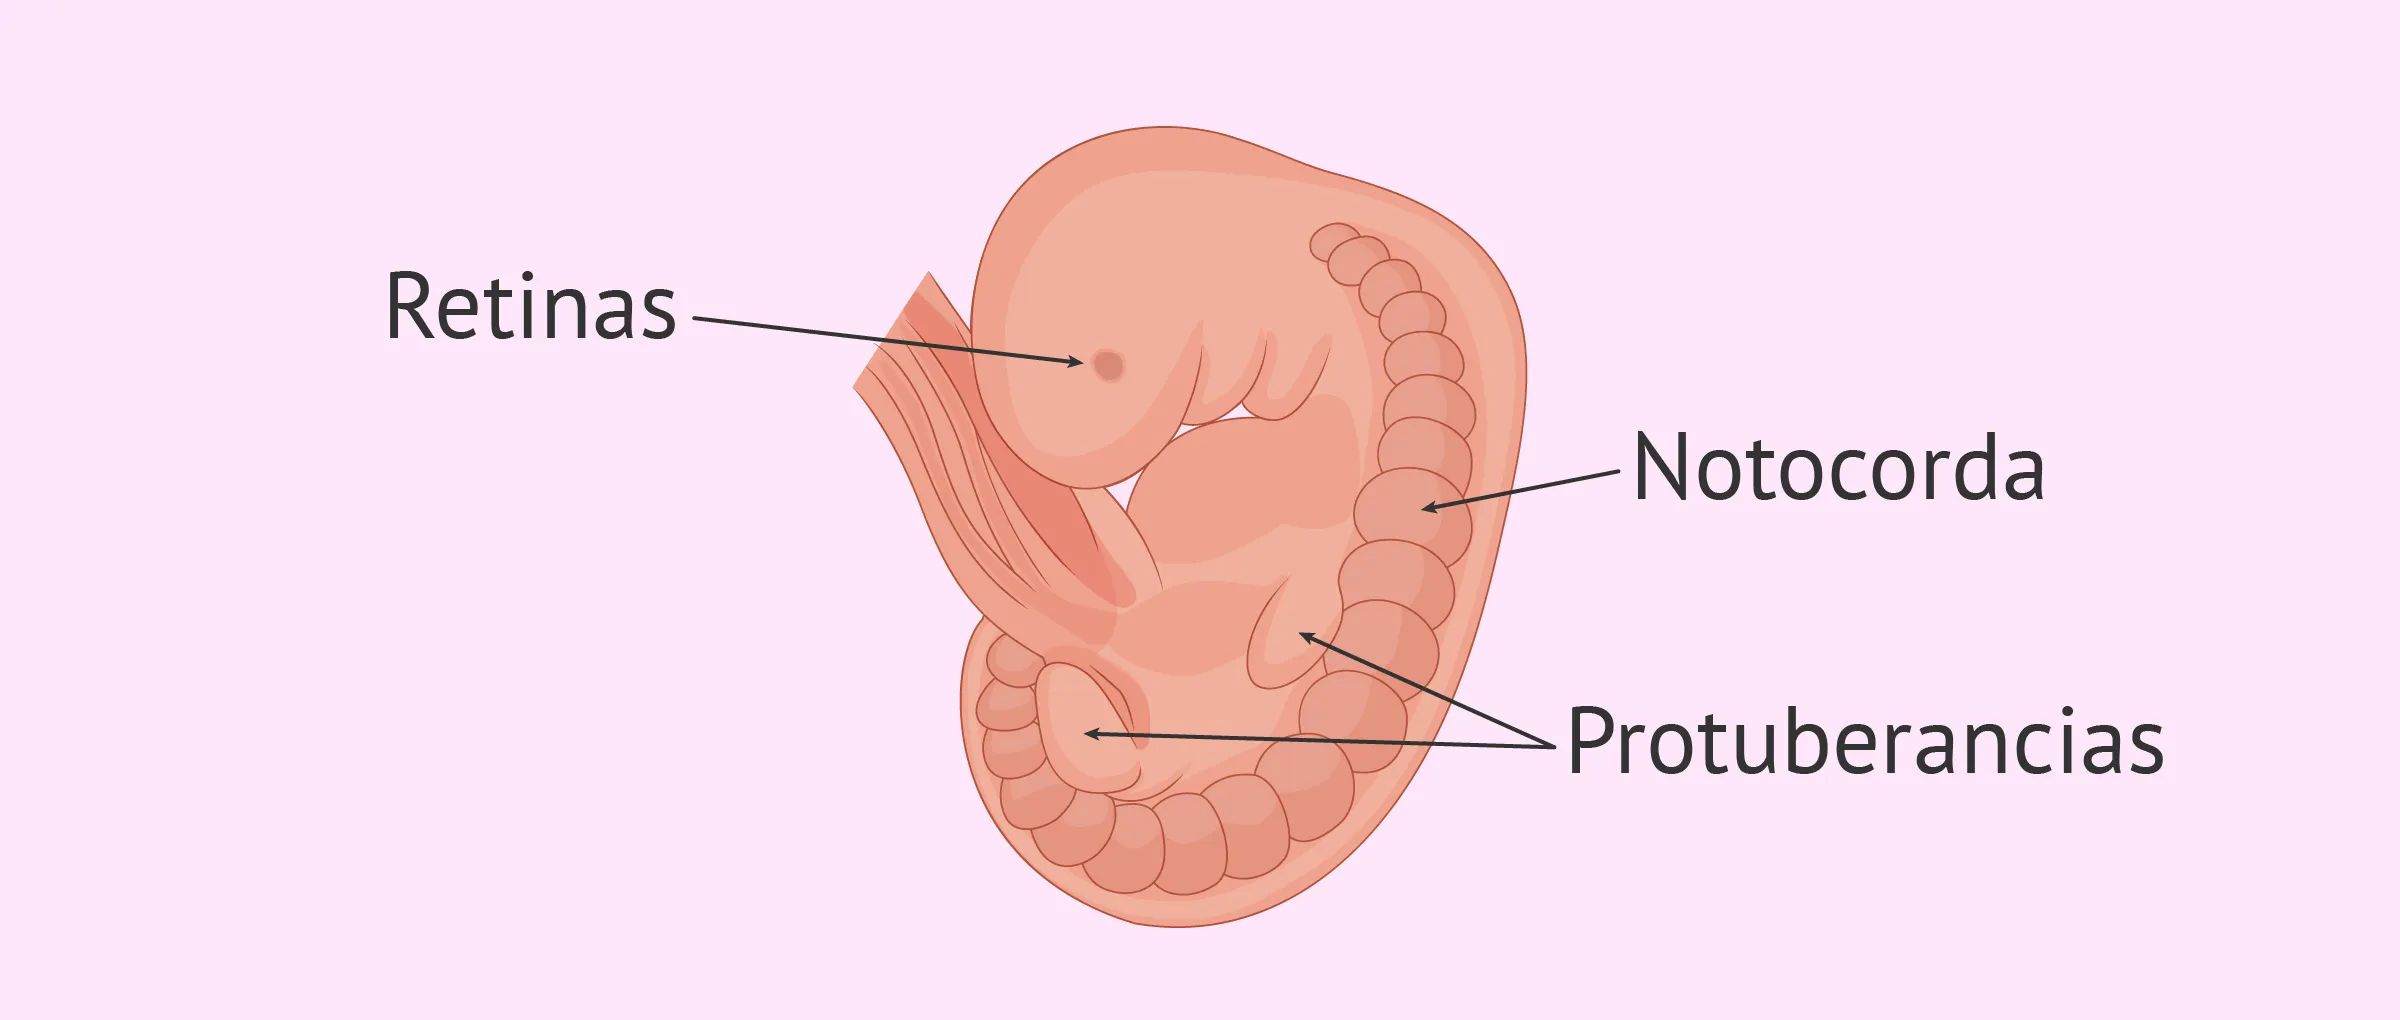

8 Semanas de embarazo: El gran paso de embrión a feto ...

Semana 6 de embarazo: evolución del embrión y síntomas